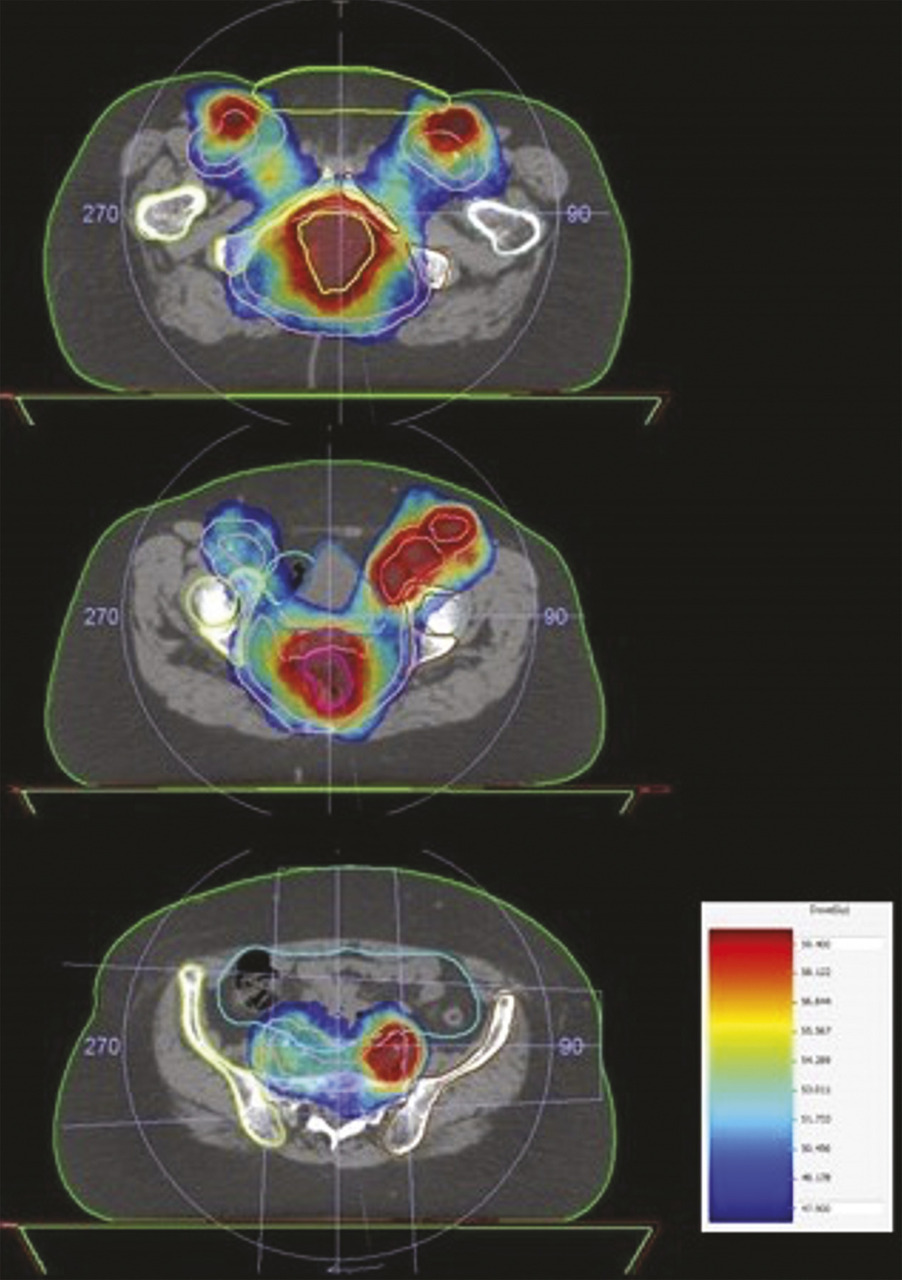

Bien que la chimiothérapie n’ait pas changé depuis quarante ans, les résultats de la chimioradiothérapie se sont améliorés, avec des survies globales de l’ordre de 80 % à cinq ans dans les derniers essais. Ces progrès peuvent probablement être attribués aux avancées techniques de la radiothérapie et des nouvelles modalités d’imagerie (IRM et TEP scanner). Ainsi, la radiothérapie conformationnelle avec modulation d’intensité (RCMI) consiste à conformer la dose au volume cible complexe (incluant la tumeur et les aires ganglionnaires inguinales et pelviennes) à traiter, tout en protégeant les organes sains (fig. 3). Cette technique précise suppose un contrôle rigoureux du positionnement du patient et du volume cible, grâce à l’imagerie embarquée présente sur les machines de traitement. Plusieurs études rétrospectives non randomisées montrent une diminution de la toxicité aiguë avec la RCMI, permettant d’éviter les interruptions du traitement pour toxicité, potentiellement préjudiciables à son efficacité. Par ailleurs, les nouvelles modalités d’imagerie, comme l’IRM et le TEP scanner, ont permis d’évaluer plus précisément le stade tumoral initial et aidé à la délinéation des volumes cibles par le radiothérapeute.